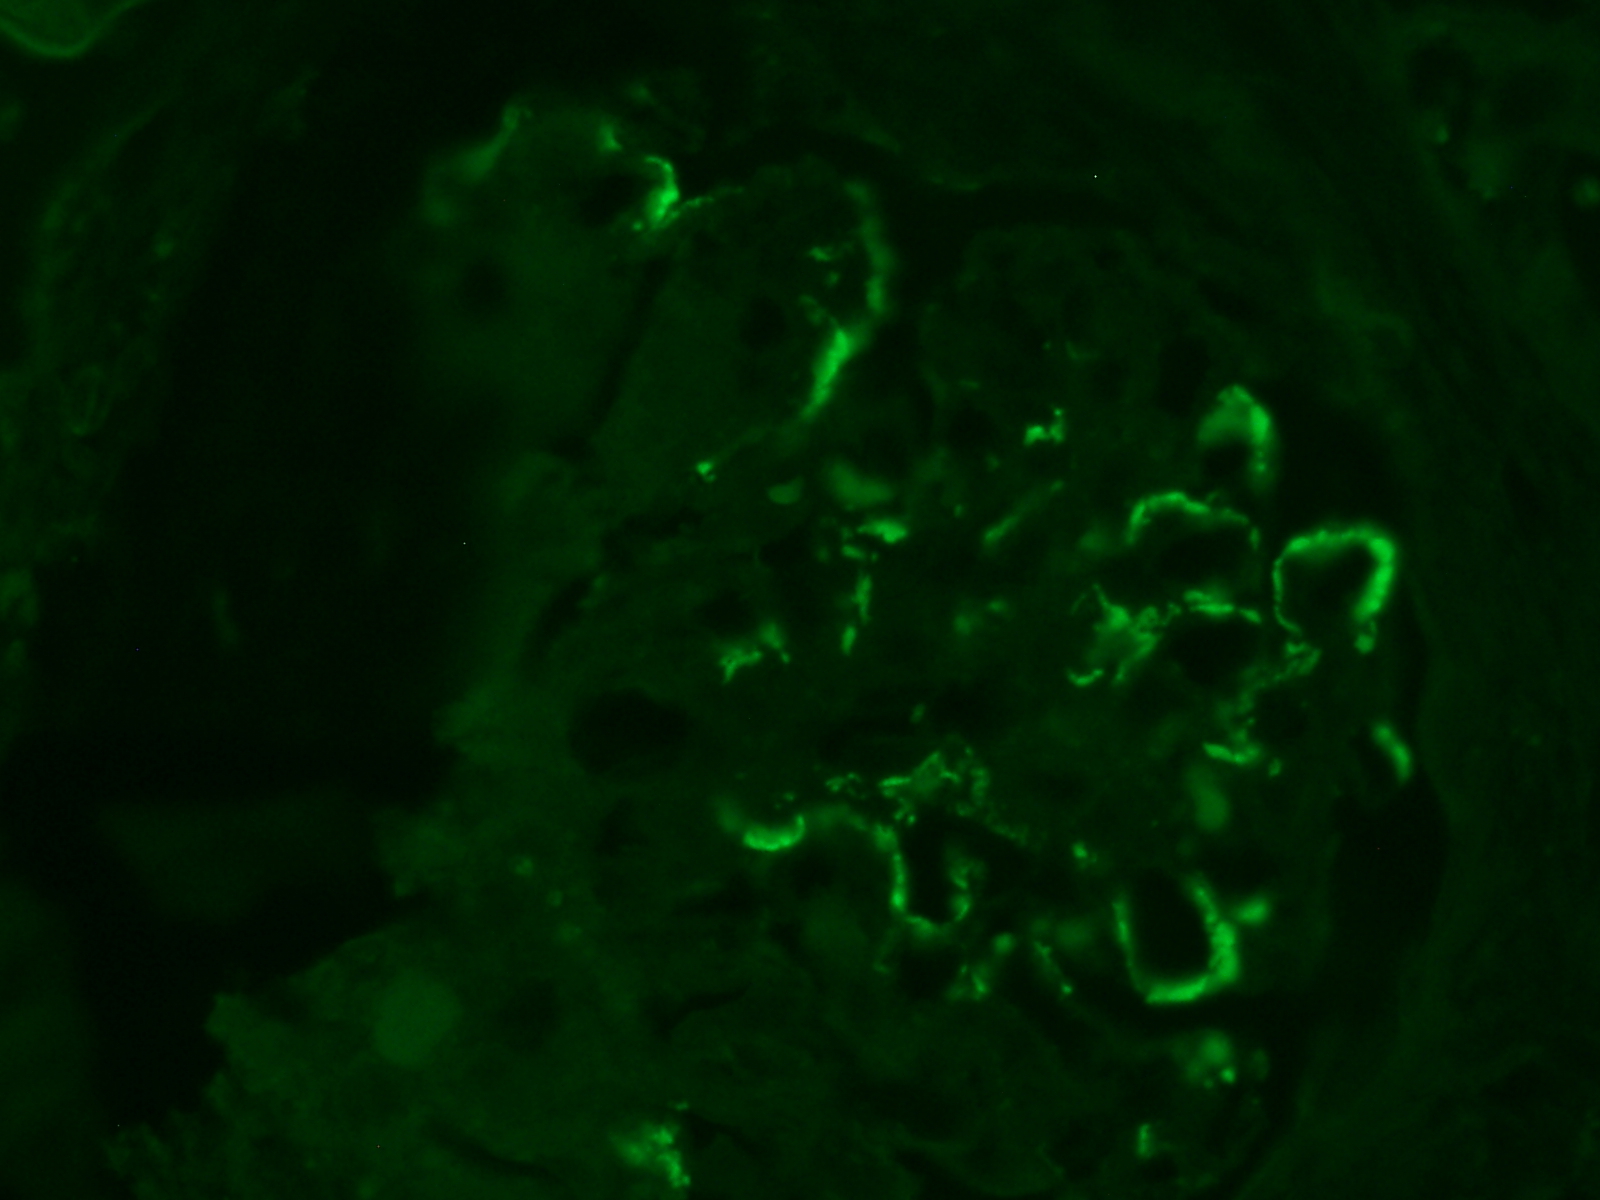

- 0.3cm - 0.5cm of cortex with glomeruli for Michel’s, IF

Acceptable alternative for Michel’s / Immunofluorescence

- flow cytometry media / RPMI

- Zeus transport fluid